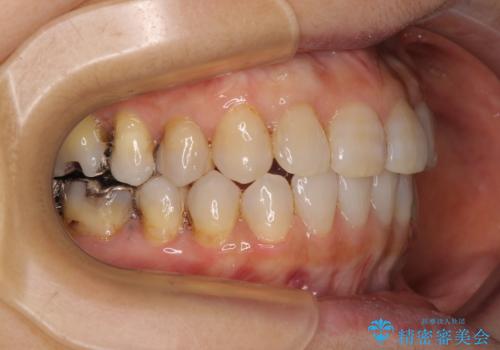

前歯の突出感と上下の隙間 インビザラインによる矯正治療

- 前歯の上下スペースと前歯の隙間を気にして来院された患者様です。

インビザラインにより上下の前歯の隙間を閉じながら、IPRを用いて口元の突出感を合わせて改善していくこととしました。

上下の隙間に舌が入り込むことが、すきっ歯やオープンバイトの原因であったため、舌の筋肉のトレーニングも並行して行い、後戻りの抑制を図りました。